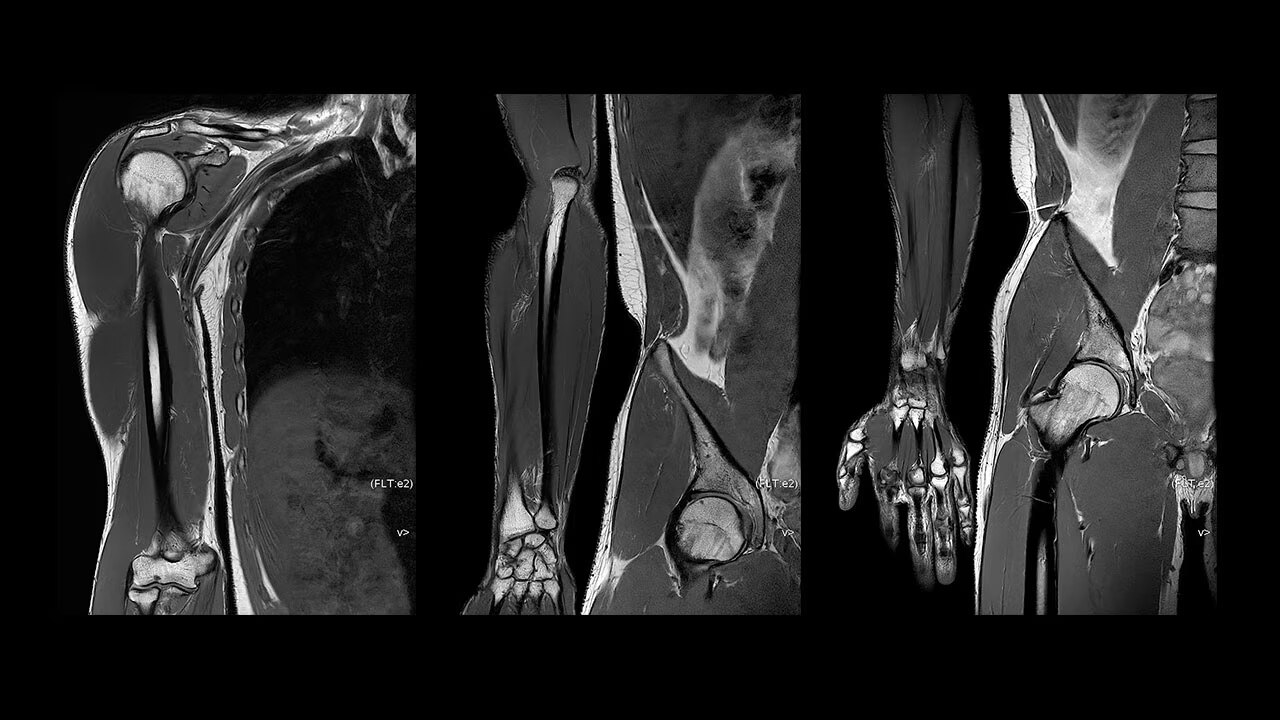

With access to the latest advanced AI technology, you can scan all anatomies and achieve pin-sharp images. Our pioneering deep learning-based reconstruction algorithm AIR Recon DL accelerates scan time and puts patients at ease.